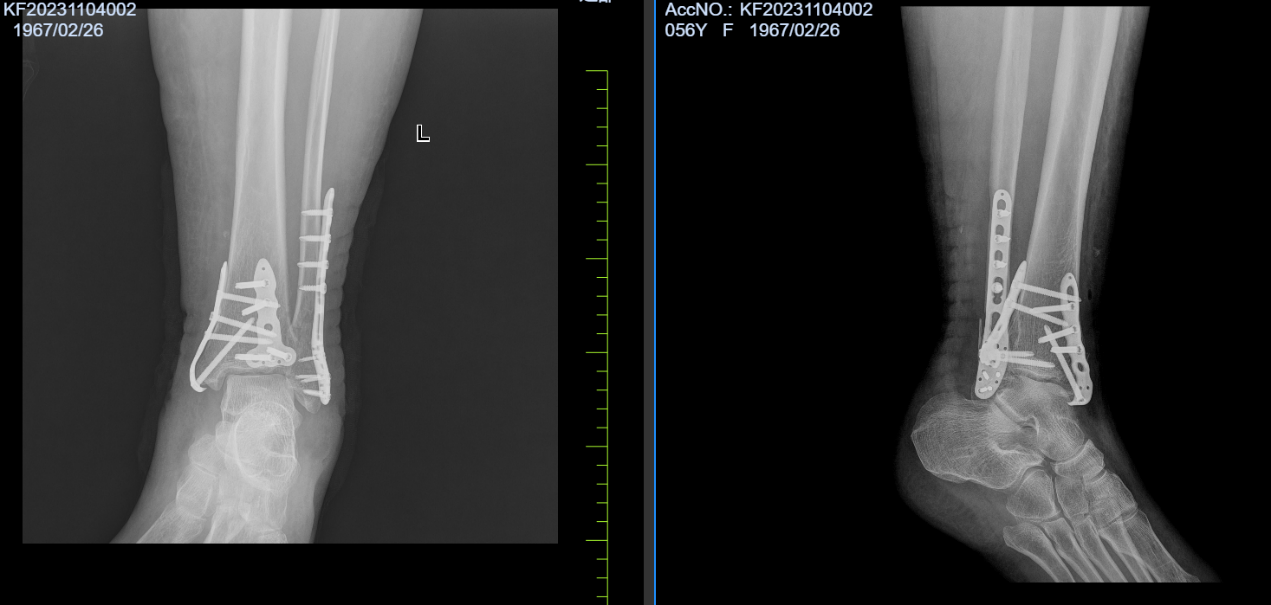

病例五:患者,女,56岁,因“车祸伤致左踝关节肿痛伴活动受限14小时”入院。诊断:左侧三踝粉碎性骨折伴踝关节脱位;行左踝关节骨折切开复位内固定术;手术顺利,术后进行康复训练中,功能恢复良好。

左侧三踝粉碎性骨折 术前X线片

左侧三踝粉碎性骨折 术后X线片